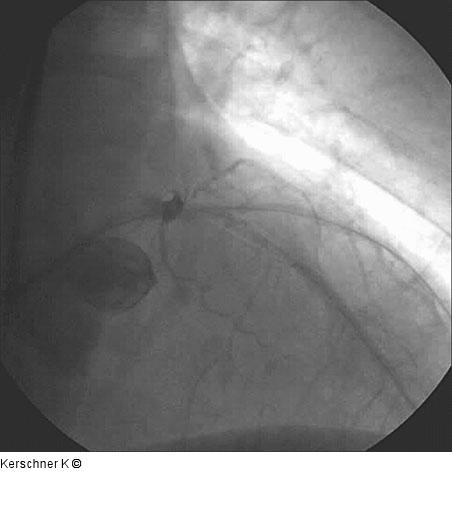

Abbildung 5: Vordilatation - Ergebnis Ergebnis nach Vordilatation. |

Ergebnis nach Vordilatation. |